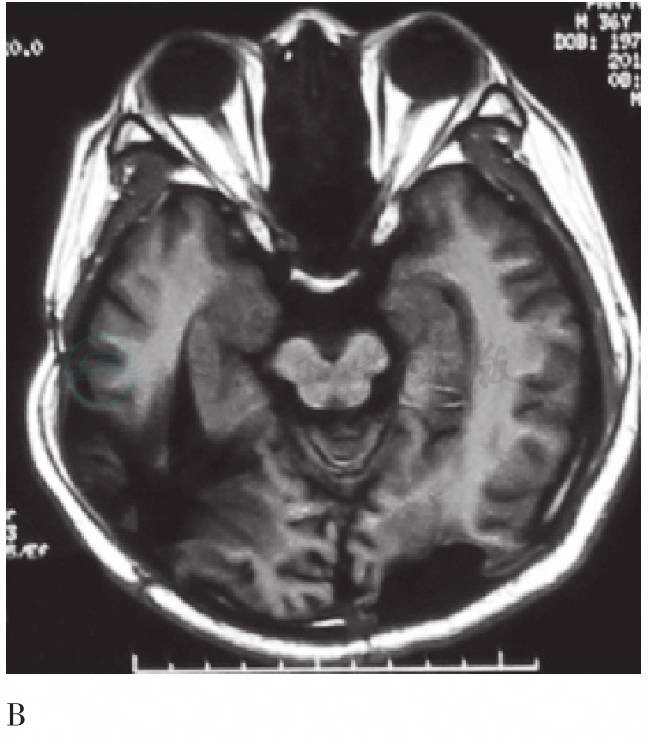

图1 MRI示脑内病变的术前、术后对比

A. 术前T2加权MRI示双侧枕叶多发病变(箭头);B. 手术后T1加权MRI示上述病变全切术后改变